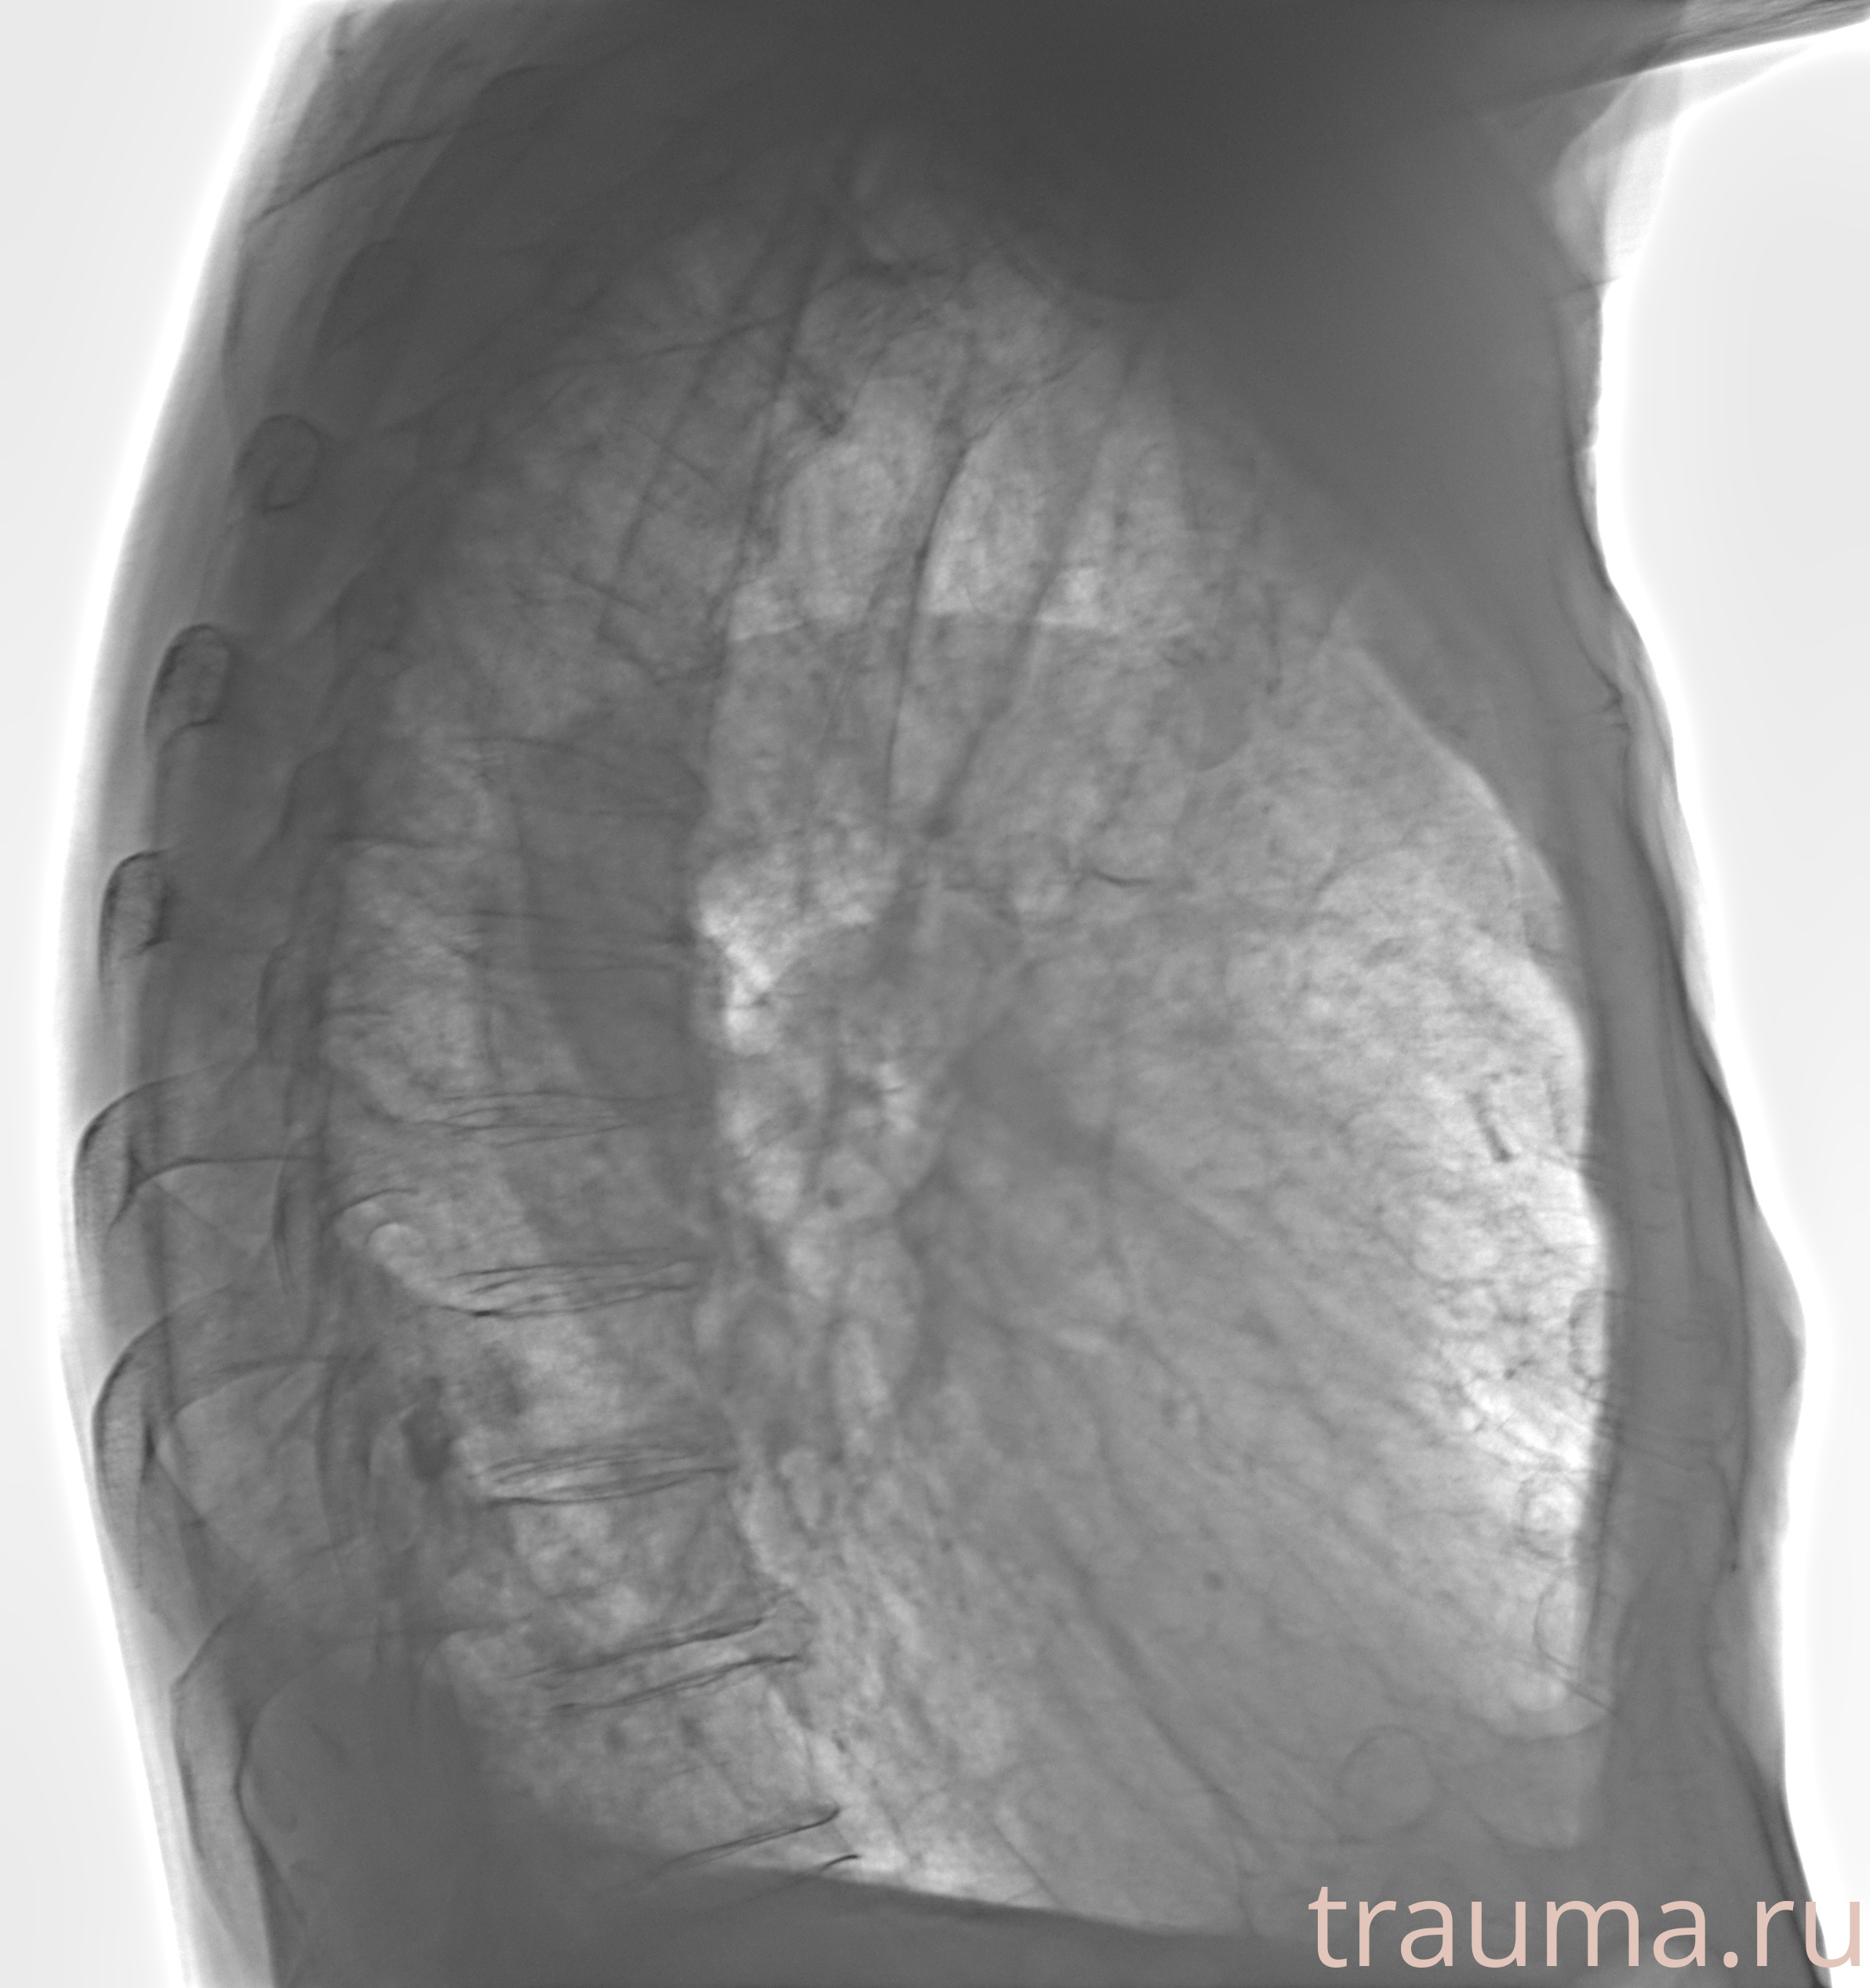

Рентгенограммы

Рентген на дому: по вашему адресу приезжает врач-рентгенолог, травматолог-ортопед с мобильным рентгеновским аппаратом, проводит диагностику травмы или заболевания, делает необходимые рентгенограммы, дает рекомендации по дальнейшему лечению. Получить качественные снимки в домашних условиях возможно благодаря уникальной методике, разработанной МосРентген Центром для института  Склифосовского